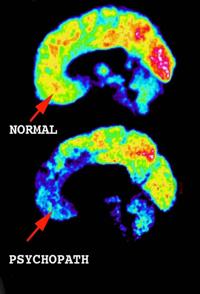

公众非常重视精神疾病。精神变态带有令人恐怖的暴力性,估计英国有30至40万精神变态者,教授Uta Frith研究精神错乱的案例,包括英国著名谋杀犯Ian Brady的精神分析。但什么是精神病?到底是什么驱使他们造成伤害,甚至杀死?他们能治愈吗?